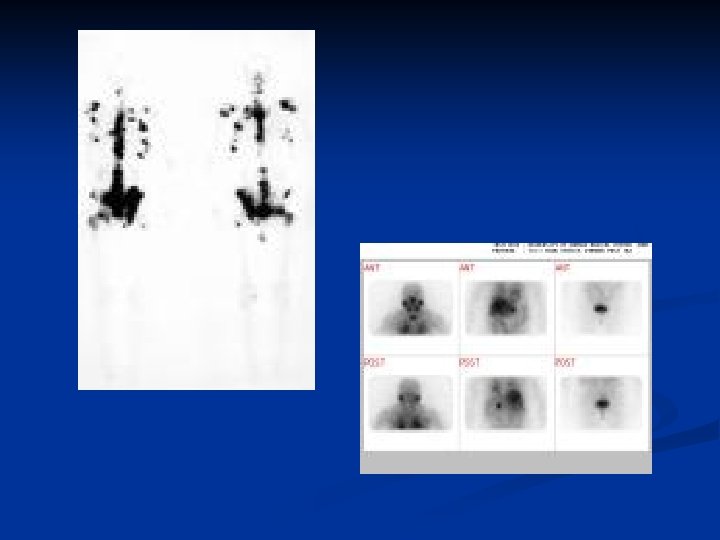

Diagnosis n n n With locally advanced tumors diagnosis can be confirmed by rectal examination Features include hard nodule or loss of central sulcus Transrectal biopsy should be performed Multi-parametric MRI maybe useful in the staging of the disease Bone scanning may detect the presence of metastases Unlikely to be abnormal if asymptomatic and PSA < 10 ng/ml

Investigation n n o o o Diagnosis can often be confirmed by testicular ultrasound Pathological diagnosis made by performing an inguinal orchidectomy Disease can be staged by thoraco -abdominal CT scanning Tumor markers are useful in staging and assessing response to treatment Alpha-fetoprotein (alpha FP) n Produced by yolk sac elements n Not produced by seminomas Beta-human chorionic gonadotrophin (beta HCG) n Produced by trophoblastic elements n Elevated levels seen in both teratomas and seminoma LDH